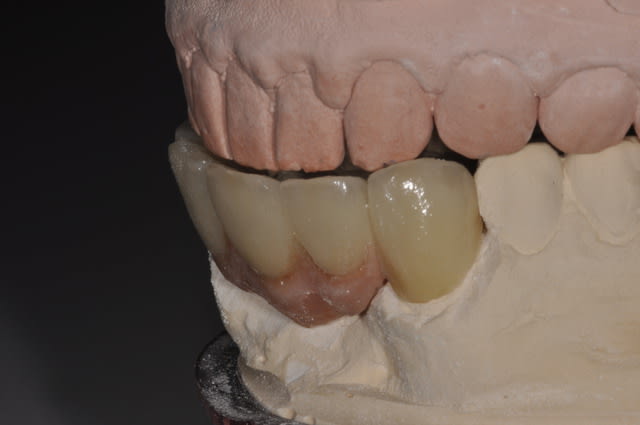

J'ai revu le patient au bout d'un an.

Je vous ai mis des photos du labo, puis 1 semaine après la pause et enfin celles de la semaine dernière.

Méthode développée par mr pretau en italie et maintenant commercialisée par Zirkonzhan.

Voir leur site : http://www.zirkonzahn.com/fr/Default.aspx

l'armature metallique ne sert que pour l'essayage et après elle est dupliquée en armature zircone et enfin montage du cosmetique.